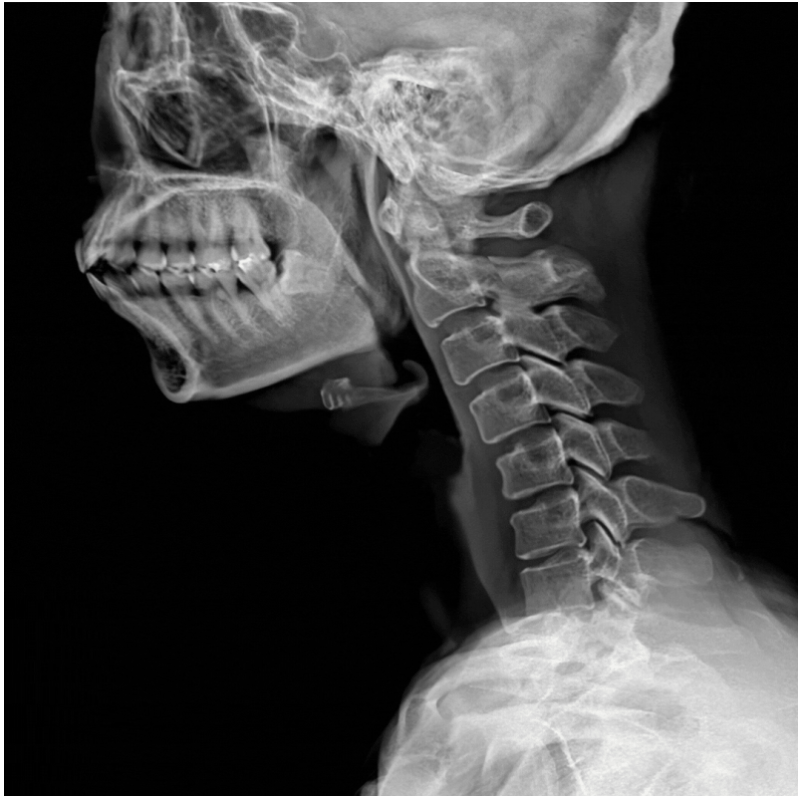

정상적인 목뼈는 앞쪽으로 완만하게 휘어진 C자 곡선을 유지합니다. 이 곡선이 약 5~6kg에 달하는 머리 무게를 여러 방향으로 분산시켜줘요. 그런데 모니터를 보며 목을 앞으로 내미는 자세가 반복되면, 이 곡선이 서서히 펴지기 시작합니다. 일자목에서 거북목으로, 거북목에서 구조적 변형으로 단계적으로 진행되는 거예요.

의학적으로는 경흉추 이행부 후만 변형(cervicothoracic kyphosis)에 해당하며, 이 단계까지 이르렀다는 건 목뼈의 정렬이 단순히 ‘조금 틀어진’ 수준이 아니라는 뜻입니다.

X-ray로 경추 곡선과 정렬 상태를 파악하고, MRI로 디스크와 신경 상태를, CT로 뼈의 구조적 변화를 살펴봅니다. 팔 저림이나 손 기능 이상이 있다면 신경전도검사(EMG/NCV)로 손상 정도까지 객관적으로 평가할 수 있어요.